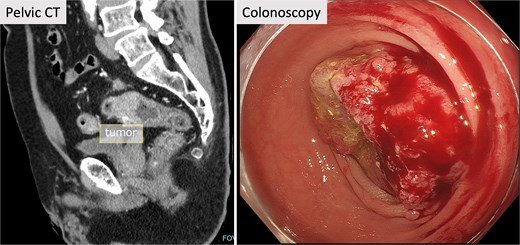

A 71-year-old male patient presented to our hospital with complaints of abnormal bowel movements. He had a history of laparoscopic cholecystectomy and had been previously diagnosed with congenital SIT (Fig. 1). Pelvic computed tomography (CT) showed a tumor in the upper rectum (Fig. 2). Colonoscopy revealed rectal stenosis due to the tumor (Fig. 2); and biopsy confirmed a diagnosis of moderately differentiated adenocarcinoma. Preoperative assessments indicated an absence of distant metastasis; therefore, robot-assisted surgery (RAS) was planned, despite the presence of SIT.

Pelvic CT and colonoscopy. Pelvic CT showed a tumor in the upper rectum, and rectal stenosis with the tumor was observed in colonoscopy.